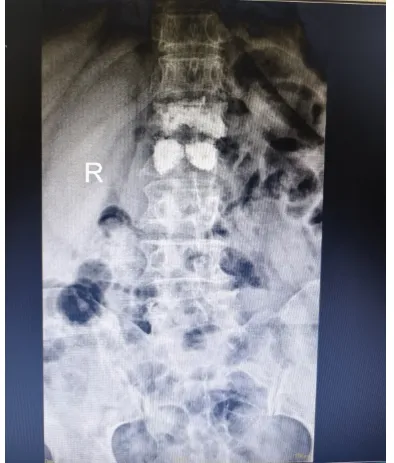

目前脊柱椎體成形手術(shù)是針對骨質(zhì)疏松所致的壓縮性骨折,椎體腫瘤等椎體壓縮性或病理性骨折所做的一種微創(chuàng)手術(shù)。椎體成形術(shù)對患者的疼痛緩解率較高,許多患者備受腰酸背痛的困擾,在手術(shù)后很快就感覺到疼痛的明顯緩解,手術(shù)在局麻下進(jìn)行,創(chuàng)傷小、安全性高,術(shù)后數(shù)小時(shí)即可下地活動,有效避免了術(shù)后可能發(fā)生的神志障礙,也避免了因長期臥床引起的褥瘡、肺炎等并發(fā)癥,尤其適合于老年患者。